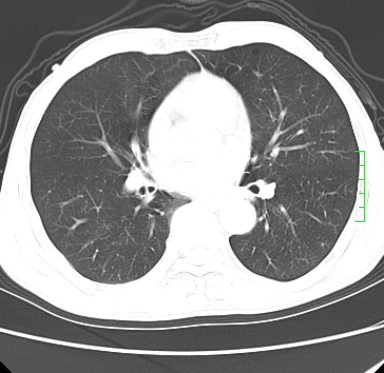

m,73y。膝关节疼痛伴双下肢水肿。入院常规胸片发现结节灶。增强为静脉期。

浅分叶、棘突,考虑右下肺周围型肺癌

考虑周围型肺癌  ,双上肺结核。

肿块周围可见局限性气肿,考虑肺癌可能性大。双肺上叶继发型肺结核。

指套征,强化明显,近侧肺组织局限性肺气肿,考虑支气管类癌,慢支、肺气肿、双上陈旧性tb、冠脉钙化。

鉴别:先天性支气管闭锁,变态反应性支气管肺曲霉菌病,肺癌,支气管囊肿,支扩黏液嵌塞。

1)考虑右肺下叶周围型肺癌。2)右肺上叶及左肺感染性病变(结核可能)。3)肺气肿。4)冠状动脉钙化。